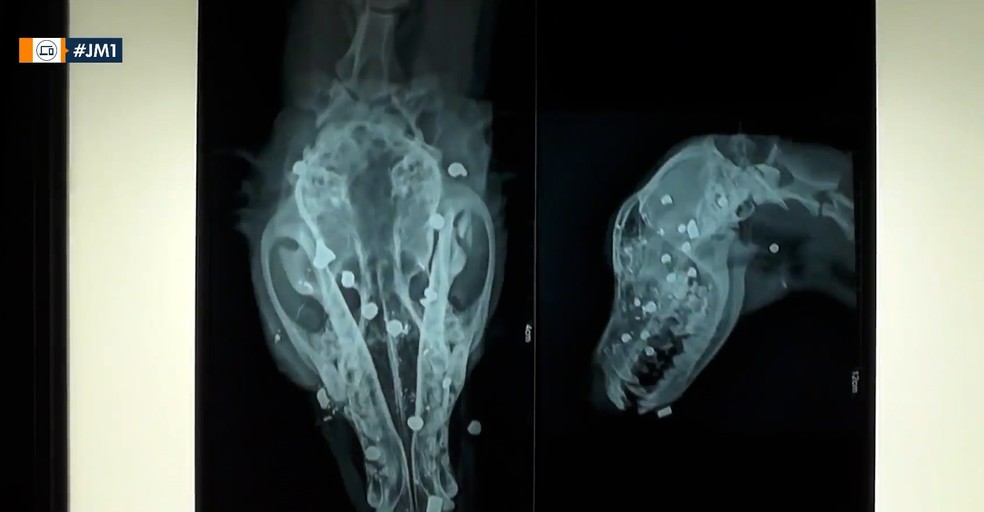

Cachorro foi atingido na cabeça com caroços de chumbo, em Bacabal — Foto: Reprodução/Redes sociais

Um homem, ainda não identificado, atirou contra um cachorro com uma espingarda n Zona Rural de Bacabal, a cerca de 240 km de São Luís.

Até o momento, ainda não se sabe o motivo do criminoso ter atirado contra o animal, que foi atingido por vários caroços de chumbo, na região da cabeça.

Os primeiros socorros foram prestados por um adestrador da cidade, até que o cão foi levado para uma Organização Não-Governamental que cuida de cachorros abandonados. O adestrador conseguiu retirar alguns caroços, mas os demais se mantiveram por estarem em locais de difícil acesso.

O animal está internado em uma clínica e corre o risco de ficar cego. No Brasil, o ato de maus tratos a animais é crime e está sujeito a dois anos de prisão, além de proibição de ter a guarda de animais.